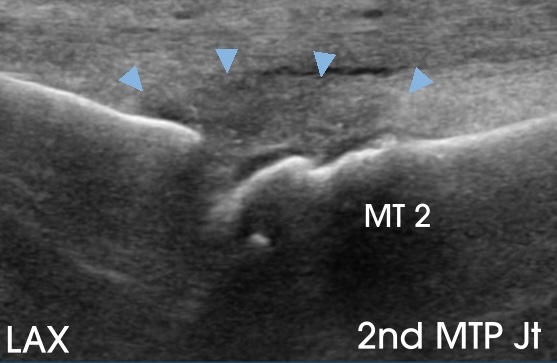

The patient’s plain radiographs demonstrated mild hallux valgus and early 1st MTP joint osteoarthosis. The LAX image below shows the 2nd MTP joint, where the joint capsule is enlarged (arrowheads).